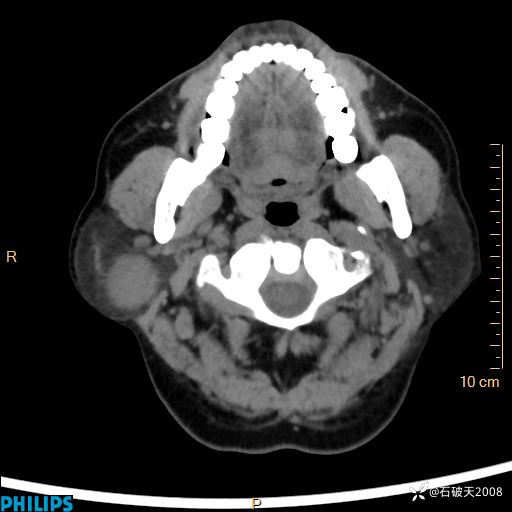

动脉期